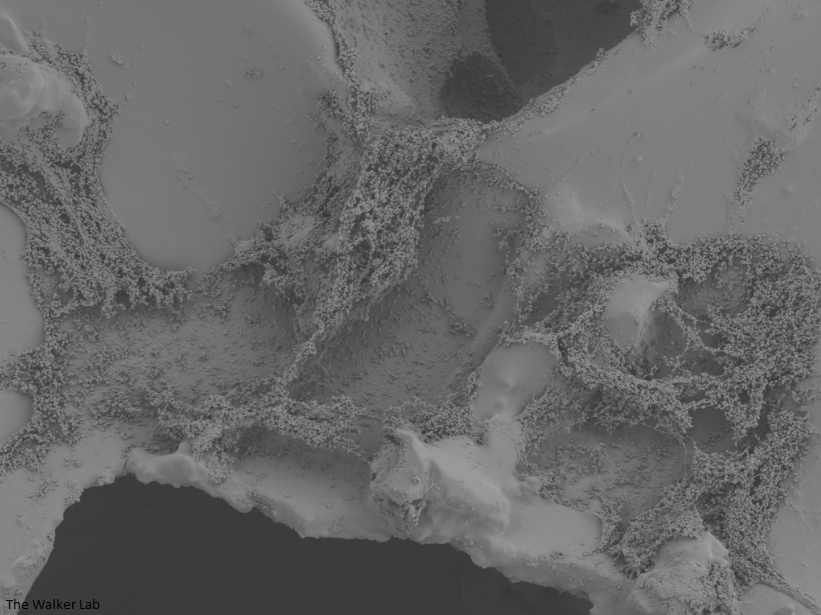

SEM Images of Mouse Catheters

Silicone urinary catheters have smooth surfaces, while latex urinary catheter surfaces are rough. Regardless of the catheter material, deposition of host inflammatory factors alters the surface and facilitates infection by atypical pathogens.

Bladder Epithelial Cells

Urinary catheters render people susceptible to atypical uropathogens. We use the atypical uropathogen, methicillin-resistant Staphylococcus aureus (MRSA), to study the catheter-host-pathogen interactions that facilitate disease.

The host inflammation response to the catheter recruits immune cells and wound healing proteins which are deposited on the catheter surface. Atypical pathogens can use these host factors to adhere to the catheter's large surface and create biofilm. Colonization of catheters occurs quicker than expected and develops even in the presence of prophylactic antibiotic therapy. MRSA is just one of the uropathogens that can attach to the altered urinary catheter surface. One host factor deposited on the catheter surface is fibrinogen. We recently discovered that MRSA binds fibrinogen to attach to the catheter surface and form biofilm, which increases antibiotic recalcitrance. Our future studies aim to develop new non-antibiotic strategies that interfere with those interactions to prevent or treat CAUTIs.